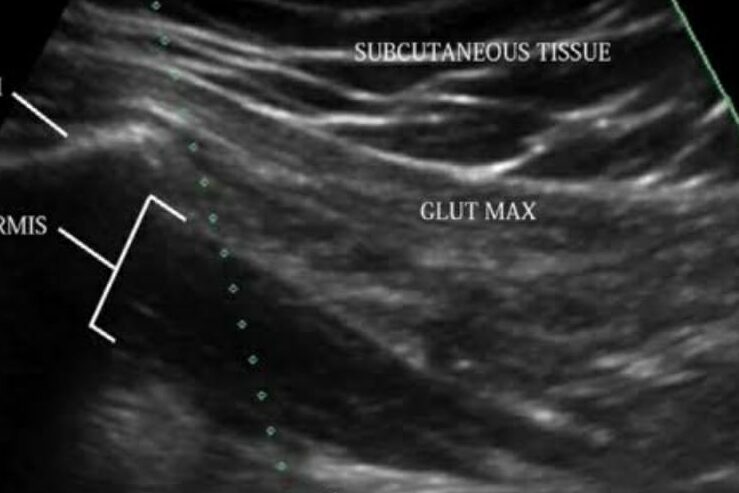

Our clinic is the first to offer world class comprehensive pain management services in Uttarakhand. All our procedures are : *Non surgical, *Painless, *Less than 1 hour duration, *Done under imaging guidance, *Performed by experienced professionals

- Hip joint

- SI joint injection of PRP/ BMC